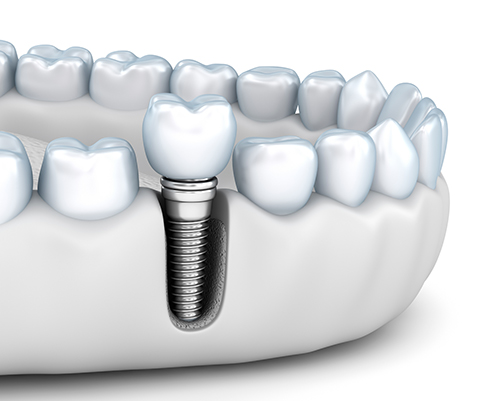

インプラント治療とは、歯を失った箇所に人工の歯根(インプラント)を埋入し、歯を補う治療法です。

上部構造(人工歯)を取り付けるためのアバットメント(土台)を装着します。

歯ぐきが安定したら、上部構造(人工歯)を取り付けます。